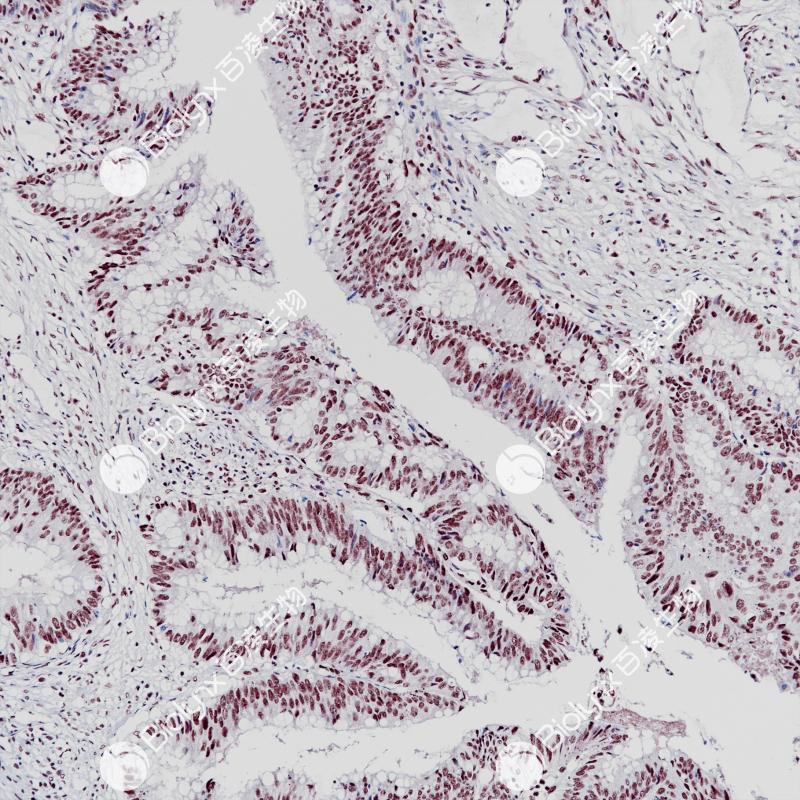

结肠癌BAP-1(BP6255)染色

BAP-1 (BRCA-1相关蛋白-1)是一种80 kDa的蛋白质,它通过靶向降解或改变其他蛋白质的活性功能来去除泛素修饰物。因此,BAP-1有助于参与调节不同细胞过程的靶蛋白功能。BAP1基因的种系突变已被确定为一种新型的肿瘤易感综合症的遗传驱动力,其导致遗传性、早发性癌症的风险增加。BAP-1与多种类型癌症的早发和/或风险增加有关,包括膜黑色素瘤、恶性间皮瘤、结肠癌和肾细胞癌。

阳性对照

结肠癌

细胞核